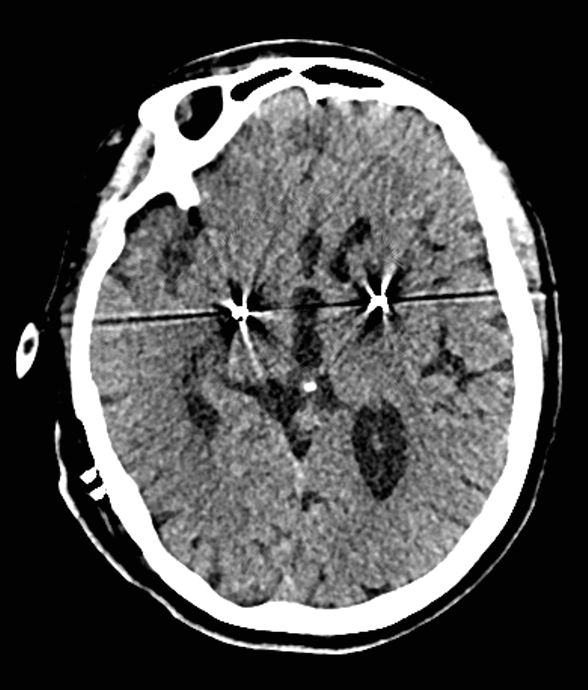

患者有家族史,基因检查显示为亨廷顿病。MRI检查显示双侧尾状核、壳核明显明显萎缩。

患者行双侧GPI DBS手术,手术顺利。下图为患者的计划,该患者大脑皮层萎缩明显、对称性尾状核萎缩,侧脑室前脚尾状核区呈球形向外膨起,呈“蝴蝶征”。这类型的患者对靶点的要求十分高,精确的确定靶点,对于术后的效果可以起到更好的作用。

术后复查CT: